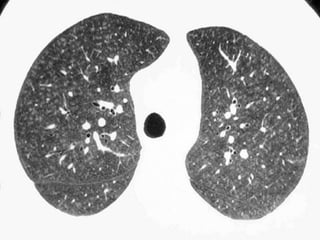

Langerhans Cell Histiocytosis

HRCT Findings

Small peribronchiolar nodules (1-5mm)

Thin-walled cysts (< 1cm),

Bizarre and confluent

Ground glass opacities

Late signs: irreversible / parenchymal fibrosis

Honey comb lung, septal thickening,

bronchiectasis

1 year later

Peribronchiolar Nodules Cavitating nodules and cysts

Langerhans Cell Histiozytosis

Key Features

Upper lobe predominance

Combination of cysts and noduli

Characteristic stages

Increased Lung volume

Sparing of costophrenic angle